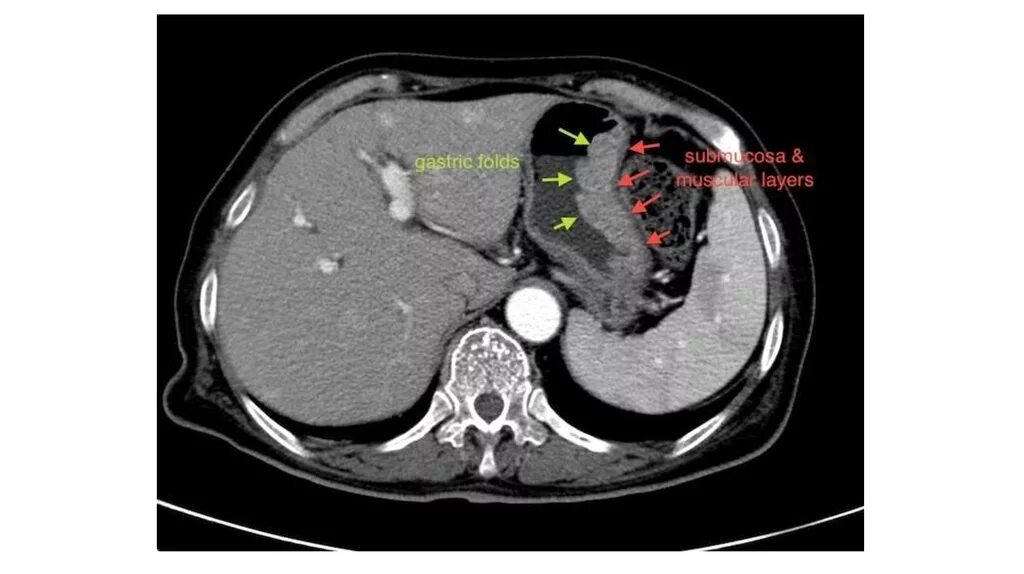

Ошибки кт